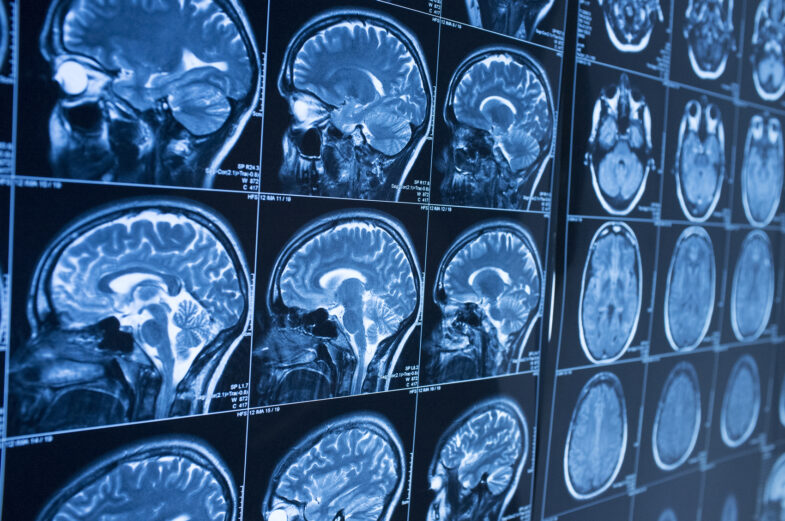

Doctors cannot confirm CTE during life. A full diagnosis requires a brain autopsy after death. Still, doctors can assess symptoms and risk factors to provide a likely diagnosis.

Scans may show brain damage, but no single test proves CTE. Doctors look for patterns. These include depression, poor impulse control, memory problems, and changes in behavior. People who played contact sports or suffered repeated concussions face higher risks.